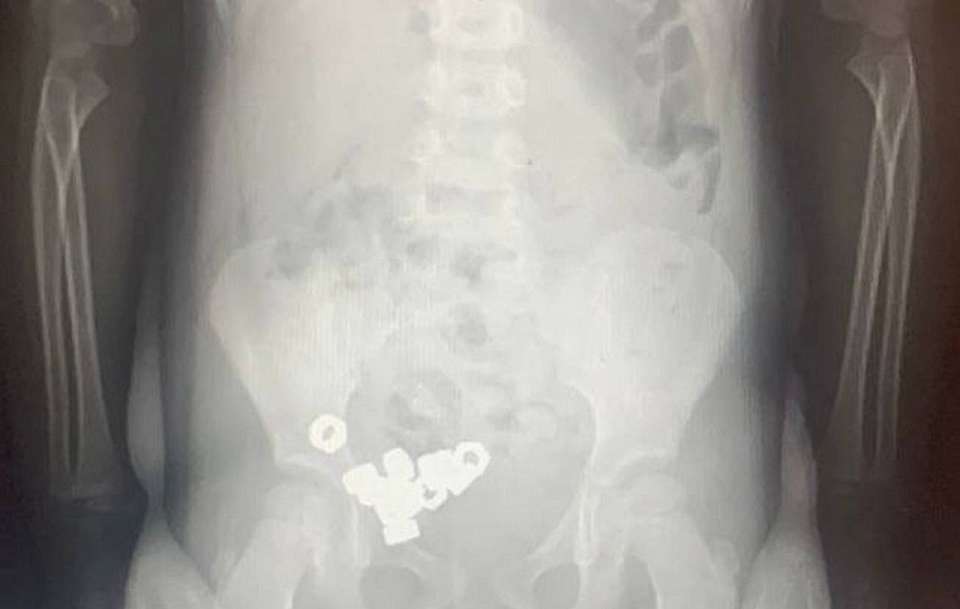

Осмотр не выявил каких-либо специфичных симптомов, однако проведённый рентген органов живота зафиксировал присутствие множества контрастных теней (шестнадцать небольших гаечек) внутри пищеварительного тракта ребёнка, сообщили в региональном Минздраве.

Ребёнок был госпитализирован для постоянного мониторинга состояния ввиду потенциальной угрозы возникновения серьёзных последствий. Поскольку обнаруженные инородные объекты не обладали магнитными свойствами и не представляли собой химически агрессивные вещества, специалисты приняли решение о проведении консервативного лечения: рекомендована специальная диета, постельный режим, наблюдение за характером испражнений и периодическое проведение повторных рентгенологических исследований.

Спустя три дня абсолютно все попавшие внутрь малыша гайки благополучно покинули организм естественным образом, вследствие чего мальчик был отпущен домой.